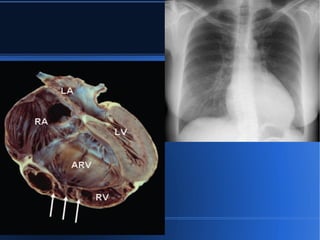

ANOMALÍA DE EBSTEIN DEFINICION ● Es una malformación que se caracteriza por un desplazamiento apical y displasia de la valva septal de la válvula tricúspide, dentro del VD debido a una inserción anómala de los velos tricuspideos. ● Exposición materna en el 1er trimestre a carbonato de litio (psicosis maniaco depresiva).

ANOMALÍA DE EBSTEIN PRUEBAS DE LABORATORIO ● ECG: bajo voltaje, p picuda en II y V1 (dilatación de AD), PR prolongado, WPW, V1 rsr´ y BRD, aleteo auricular y FA, o normal. ● Rx. torax: convexidad derecha por aumento de AD y convexidad izquierda por dilatación del infundíbulo “botella de agua”. ● ETT: ● Angiografía: EC o HTP. ● RMN: volumen y funcionamiento del VD. ●